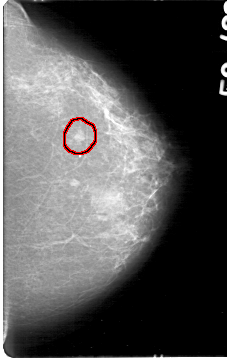

D_4047_1.RIGHT_MLO

FILE: D_4047_1.LEFT_MLO.OVERLAY

TOTAL_ABNORMALITIES 1

ABNORMALITY 1

LESION_TYPE MASS SHAPE OVAL MARGINS OBSCURED

ASSESSMENT 0

SUBTLETY 4

PATHOLOGY BENIGN

TOTAL_OUTLINES 1

BOUNDARY